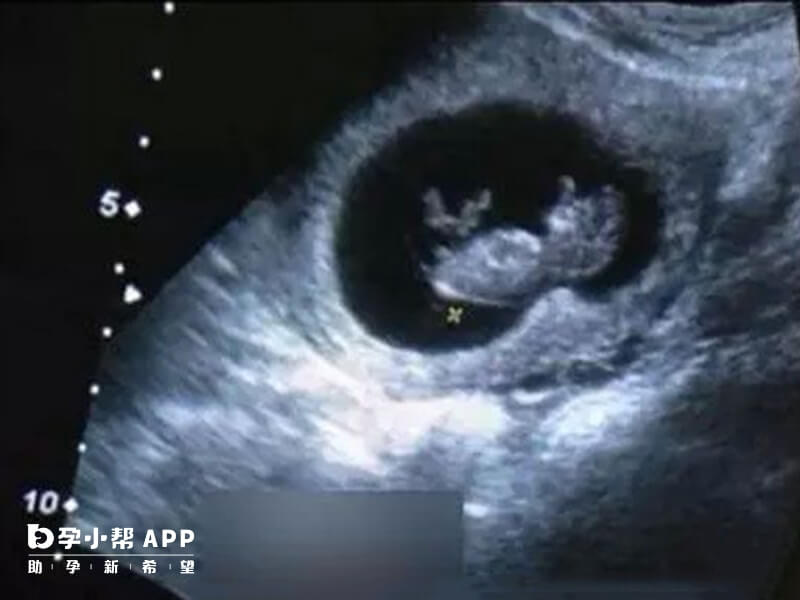

作为孕前期出镜率最高的nt检查来说,从nt检查报告单内容中可以很直观地了解到自己的胎儿发育是否正常,但是nt值只是作为粗略判断的依据,不可作为确诊手段。

正常情况下胎儿的NT值应小于2.5mm,如果NT值大于2.5mm则提示胎儿可能存在染色体异常的情况,此时胎儿可能患有唐氏综合征,因此NT2.8mm属于异常情况,建议孕妇及时前往医院完善相关检查,如无创DNA产前检测、羊水穿刺等,如果检查结果正常,则可以继续妊娠,如果检查结果异常,则需及时终止妊娠。

作为孕妇除了需要注意日常的防护之外,相关的孕期检查也不能放松,如果检查出nt值为2.8mm,在绝大多数情况下都是不正常的,因为目前nt值的正常范围界定为2.5mm,但是也有一些孕妇本身的年龄较大,此时应当考虑孕妇本身的身体因素影响,如果符合这样的情况2.8mm也可划分为正常值。

nt正常值的界限并不是想象中那么严格,一项检查的结果可能会受到多方面因素的干扰,如在nt检查的流程中,可能存在医生操作不当或者是仪器出现故障等客观因素,可以在检查结果出来之后选择进行nt复查,尽可能排除非本身问题带来的误判现象。

和一般解决nt值偏高的方法不同的是,2.8mm代表孩子出现问题的概率并不高,所以孩子能不能要还需要进一步的检查,目前采用的方法有羊水穿刺或者是无创DNA检查。

从孕期检查流程上来讲,在nt检查流程完成之后,间隔几周之后就会选择做唐筛检查,但是由于2.8mm的nt值相对风险性较高,可以直接跳过唐筛直接选择无创DNA或者是羊水穿刺。